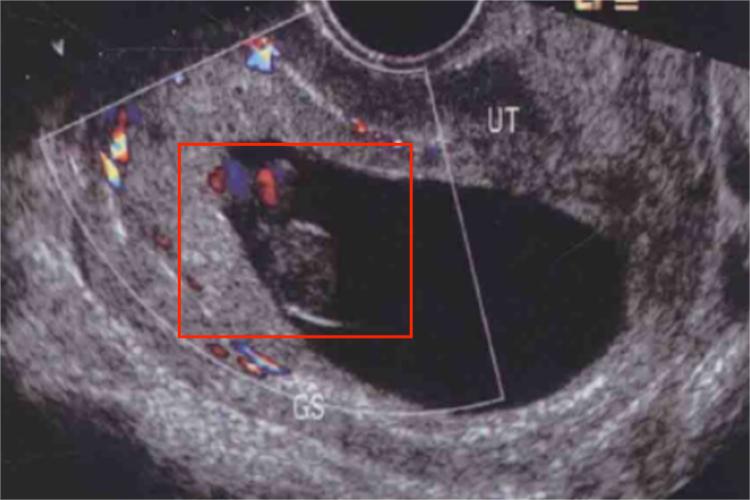

怀孕8周时胚胎初具人形,头部的大小约占胎体的一半。此时五官已能辨认,四肢已具人形,早期心脏已形成,B超检查可见胎心搏动。卵子受精后的2周内称为囊胚,8周前称为胚胎,8周后称为胎儿,故怀孕8周时胎儿仍处于胚胎状态。

怀孕8周时胚胎的手指、足趾明显,指趾出现分节,眼睑出现,尿生殖膜和肛膜先后破裂,外阴可见,但性别不分,脐疝明显。临床上常以月经龄推算胚胎龄,即从孕妇末次月经的第1天算起,但由于妇女的月经周期常受环境变化的影响,故胚胎龄的推算难免有误差,因此可根据胚胎外形推算怀孕时长。